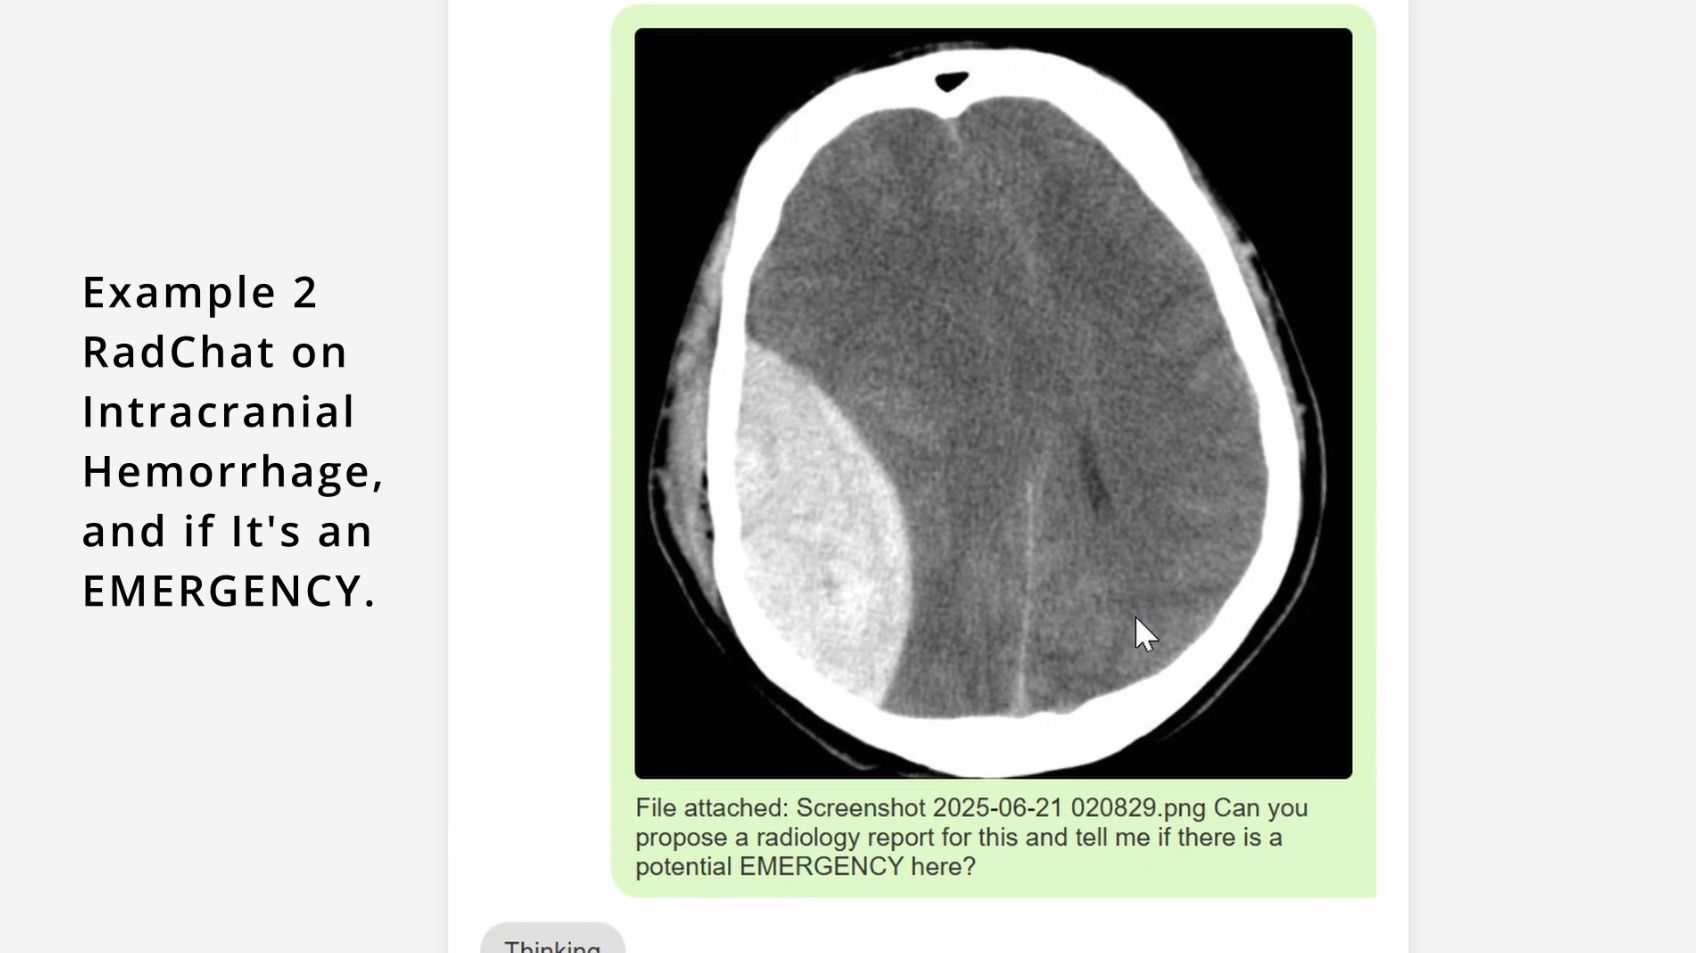

Chat bot is asked about intracranial hemorrhage and if this is an EMERGENCY.

Chat bot catches the intracranial hemorrhage, and calls it an EMERGENCY.